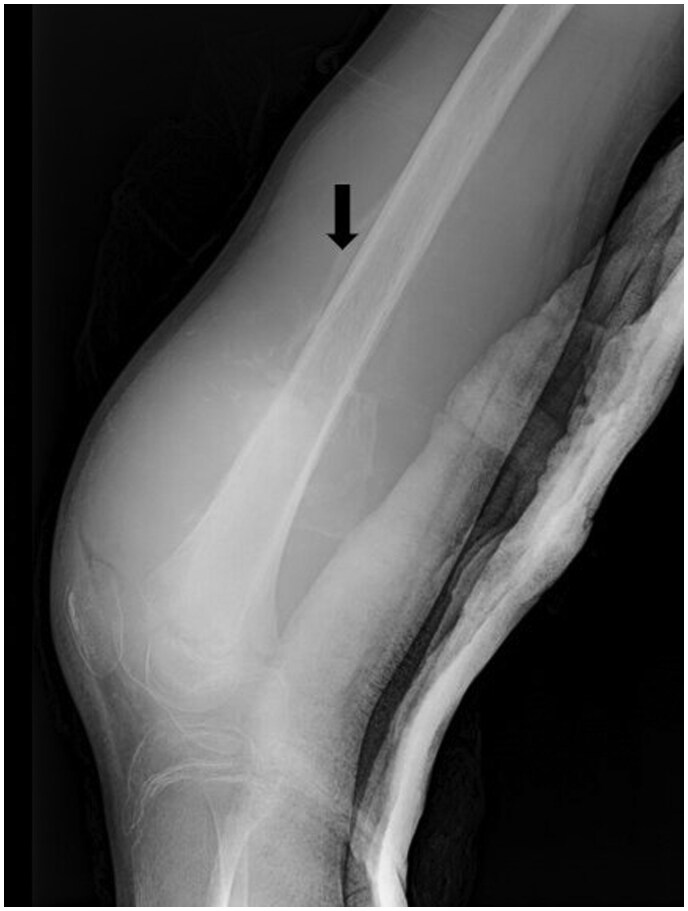

Chondromyxoid fibroma-like osteosarcoma (CMF-OS) is an exceptionally rare and low-grade variant of osteosarcoma, as classified by the World Health Organization. Misdiagnosis is common in CMF-OS, often leading to delays in definitive surgical intervention. CMF-OS exhibits variable imaging features, frequently mimicking chondromyxoid fibroma. It may present as osteolytic, osteogenic, or expansive lesions, often associated with soft tissue invasion, cortical disruption, and occasionally a periosteal reaction. Cases have been reported in diverse anatomical locations, including the craniofacial region and bones of the lower limbs. Histologically, CMF-OS is distinguished by its unique mucoid appearance, characterized by loose aggregates of stellate and spindle-shaped tumour cells embedded within a highly myxoid stroma. Surgical resection remains the cornerstone of treatment for CMF-OS, emphasizing the importance of accurate diagnosis to facilitate timely and appropriate management.